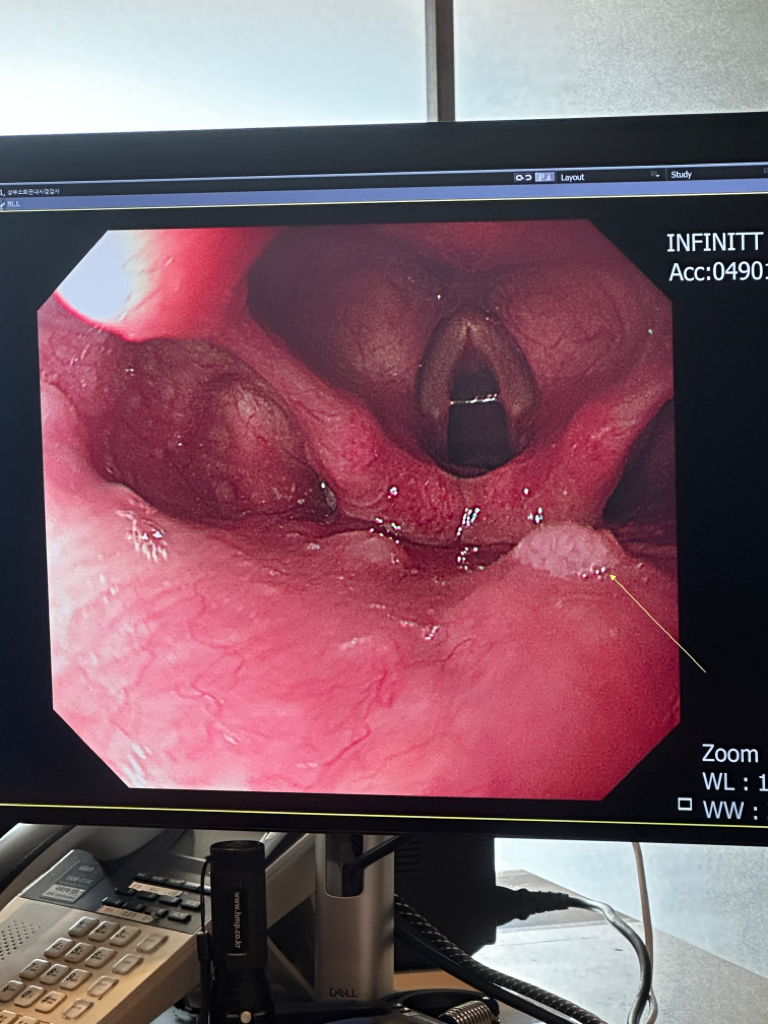

건강검진받고 이비인후과 가보라는데 심각한건가요?

건강검진 받고나서 의사선생님이 자기 분야가 아니라서 잘 모르신다고 이비인후과에 한번 가보라고 하셨는데 이게 뭔가요?????

• 1번 째 사진

혀 안쪽으로 딸기종이 생긴 것으로 보이는데 심각하기 보다는 암 보다는

일반적으로 혈관종으로 보이는데 제거가 쉬운 것은 아니어서 커지지 않는

경우, 경과를 지켜 보는 경우가 많습니다.